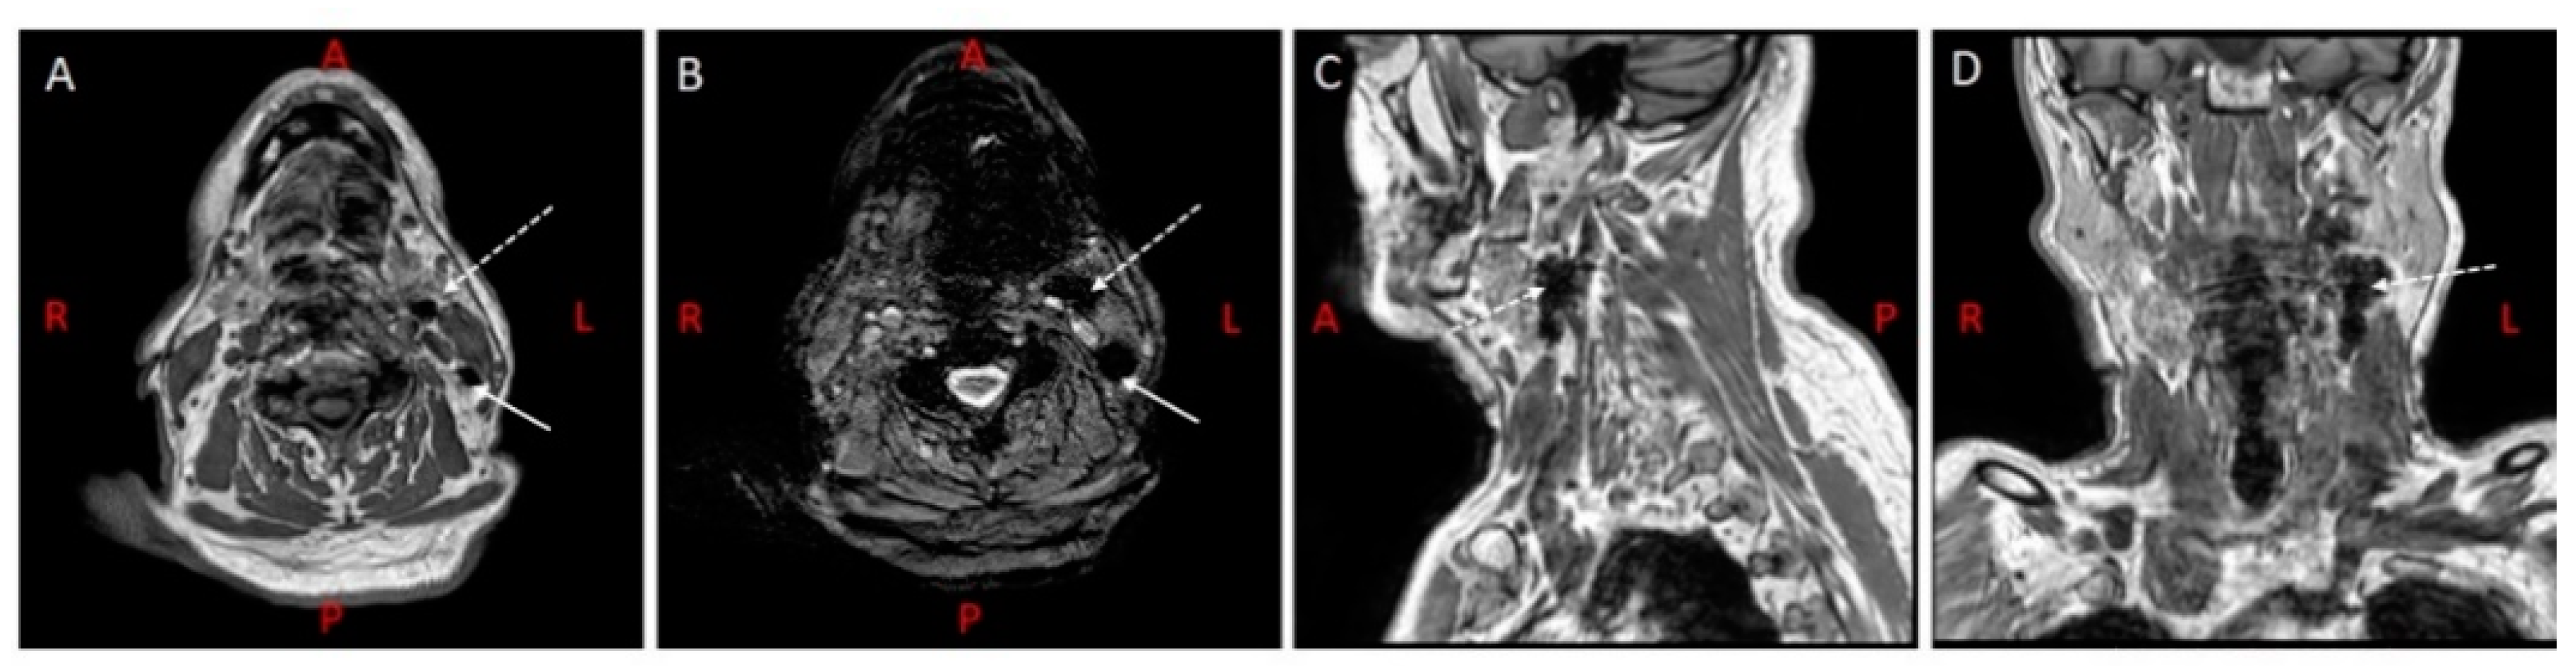

2.1. Magnetic Resonance Lymphography

3.1. MR Lymphography

4.1. MR Lymphography